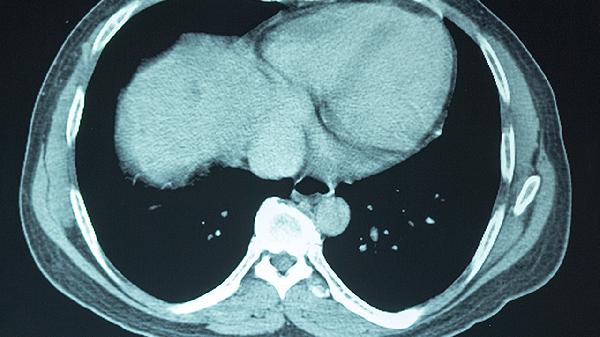

脑震荡患者需要密切观察症状变化,特别是发病后24-48小时内。若出现持续加重的头痛、反复呕吐、意识模糊、肢体无力等症状,应立即就医。医生可能会建议进行头颅CT检查,排除颅内出血等严重情况。定期随访可确保恢复进程正常,避免过早恢复活动导致症状复发。